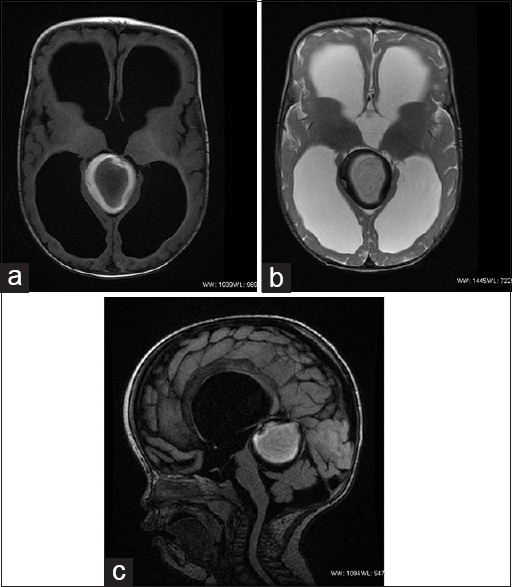

What's the Diagnosis?